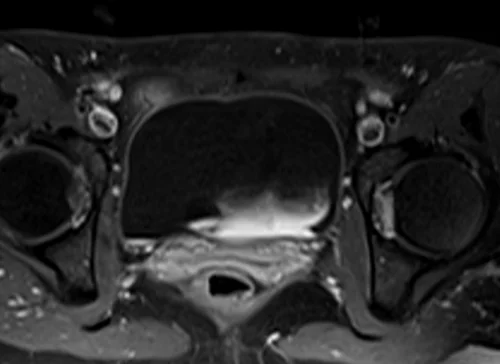

L plexus mri T1 fat saturated post contrast axial images